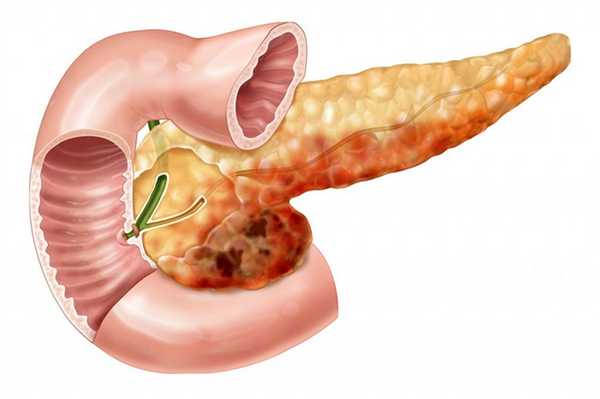

• Кистозное разделенное перегородками новообразование, образованное муцин-продуцирующим эпителием и характерной стромой овариального типа, по степени злокачественности варьирующее от потенциально злокачественных новообразований до инвазивной карциномы

о Толстостенное многокамерное кистозное образование, разделенное внутренними перегородками, и, иногда, имеющее узловатую стенку

о Тело и хвост поджелудочной железы (чаще)

о Диаметр варьирует от 2 см до > 10 см

о Средний размер 8,7 см

• Крупное образование с толстой фиброзной капсулой

• Муцин-содержащая кистозная полость:

• Не сообщается с протоком поджелудочной железы

• В полость опухоли могут пролабировать солидные папиллярные выросты